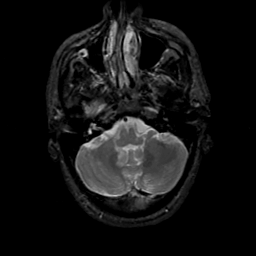

MR Study #19, August 25, 1991 -- Slice #10